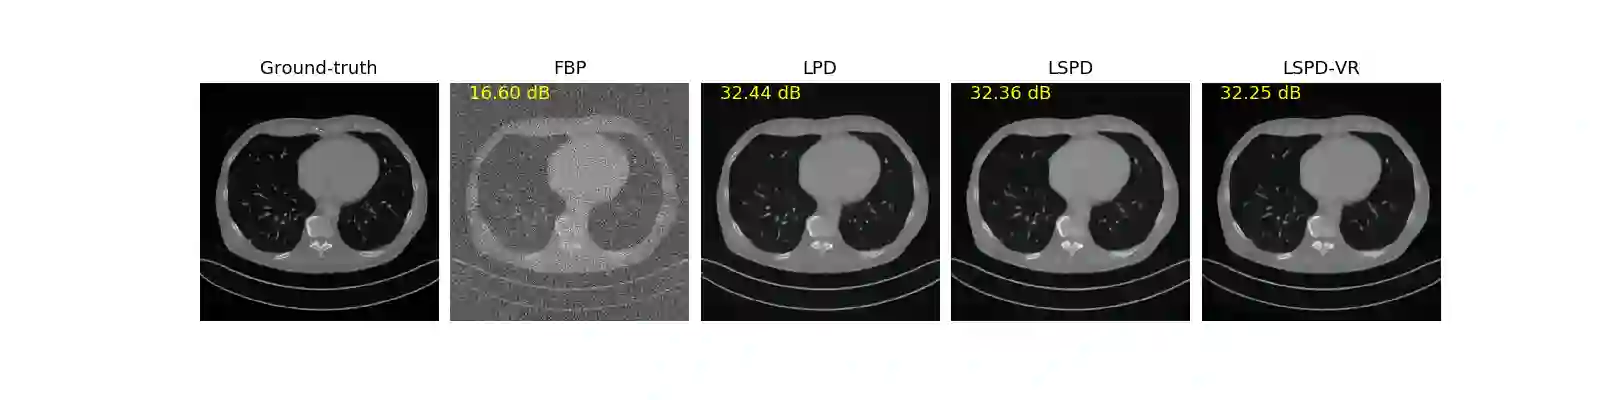

We propose a new type of efficient deep-unrolling networks for solving imaging inverse problems. Conventional deep-unrolling methods require full forward operator and its adjoint across each layer, and hence can be significantly more expensive computationally as compared with other end-to-end methods that are based on post-processing of model-based reconstructions, especially for 3D image reconstruction tasks. We develop a stochastic (ordered-subsets) variant of the classical learned primal-dual (LPD), which is a state-of-the-art unrolling network for tomographic image reconstruction. The proposed learned stochastic primal-dual (LSPD) network only uses subsets of the forward and adjoint operators and offers considerable computational efficiency. We provide theoretical analysis of a special case of our LSPD framework, suggesting that it has the potential to achieve image reconstruction quality competitive with the full-batch LPD while requiring only a fraction of the computation. The numerical results for two different X-ray computed tomography (CT) imaging tasks (namely, low-dose and sparse-view CT) corroborate this theoretical finding, demonstrating the promise of LSPD networks for large-scale imaging problems.